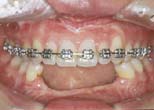

Ant. space closure or redistribution without movement of post. teeth